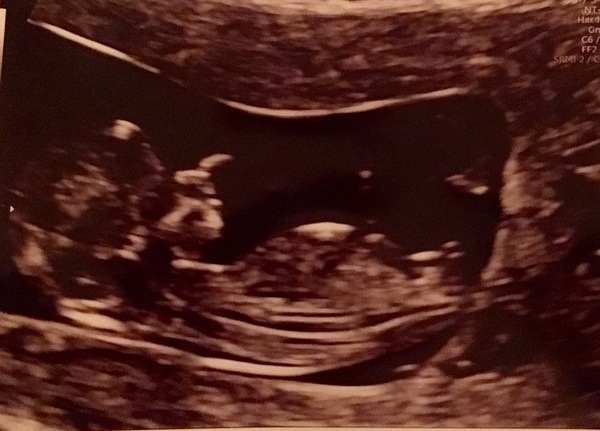

Some of you will know me from the TTC after loss thread as I have been on there over a year after 4 miscarriages ranging from 6-10 weeks. I got a BFP (seems like a while ago now) but was scared to join you all as I've always been the one who had to leave the due dates groups. This time has been slightly different as I've been under Dr Shehata on a full treatment programme, so I'm really hoping this is my rainbow. I've had regular scans from 6 weeks due to spotting and just for my own reassurance. I have attached yesterday's which was my hopefully my last EPU scan at 10 weeks 4 days and baby was measuring 11 weeks. I've got another scan Monday with Dr Shehata and I'm also having the harmony test done then too which I'm really nervous about as the last miscarriage was tested and came back as Edwards's syndrome.

I had my harmony bloods taken and had a scan. My word baby is so big compared to the little bean I met 3 weeks ago. I’m so overwhelmed. He was stretching his little legs out, bouncing around and I reckon picking his nose in this shot! I saw DH wipe away a few tears. Measuring ahead at 11w2d not 10w4d- @rubyroot you were so right, my dates were the correct ones! I did feel reassured as she said everything is measuring normally, strong heartbeat and active baby. Still anxious about the next step but happy for now :)

@Pop1234 yay! Lovely to see your poppet. So pleased to see you join. Onto the next scan :)